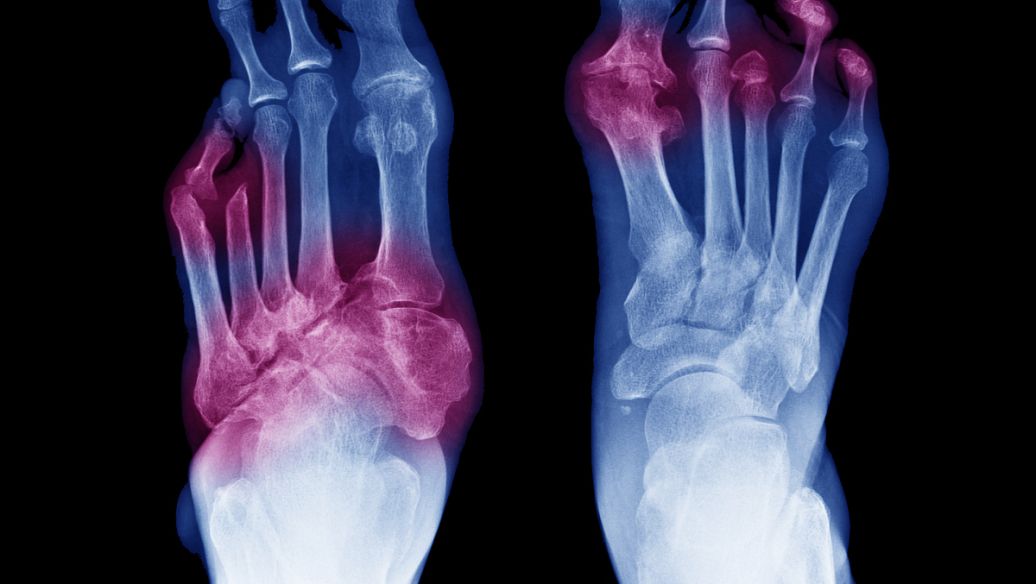

曾治苏某,女,46岁,教师。1986年4月8日就诊。患类风湿关节炎8年,经用雷公藤、布洛芬、萘普生及中药治疗均乏效。诊时双手指关节肿大变形、疼痛、屈伸不利,握物困难,晨起时痛重。有时双膝、踝关节胀痛。长期服激素类药物。舌质暗红、苔白厚腻,脉弦滑。实验室检查:血沉15mm/h,抗链球菌溶血素“0”<500 U,类风湿因子阳性。辨为热痹,治拟祛风除湿清热,通络止痛。